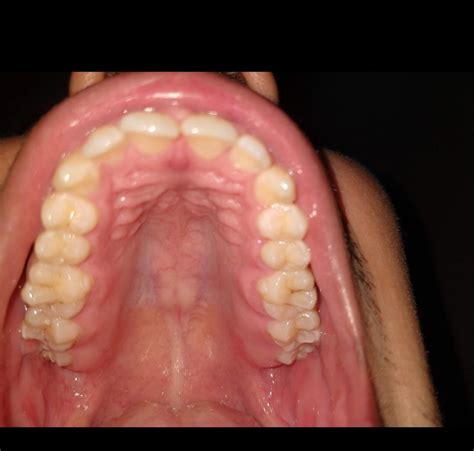

Understanding the intricacies of a high arched palate is crucial for dental professionals, speech therapists, and individuals experiencing related issues. A high arched palate, also known as a high vaulted palate or ogival palate, refers to a condition where the roof of the mouth is unusually high and narrow. This anatomical variation can have significant implications for oral health, speech development, and overall well-being.

A high arched palate is characterized by a steeply curved roof of the mouth, which can affect the alignment of teeth, the shape of the jaw, and the overall structure of the face. This condition is often congenital, meaning it is present at birth, but it can also develop due to environmental factors such as thumb-sucking, tongue-thrusting, or prolonged use of a pacifier.

Identifying a high arched palate typically involves a visual examination by a dental professional. During this examination, the dentist or orthodontist will assess the shape and height of the palate, as well as the alignment of the teeth and the position of the tongue. In some cases, additional diagnostic tools such as X-rays or 3D imaging may be used to gain a more comprehensive understanding of the condition.

Diagnosing a high arched palate typically involves a thorough examination by a dental professional. The dentist or orthodontist will assess the shape and height of the palate, as well as the alignment of the teeth and the position of the tongue. In some cases, additional diagnostic tools such as X-rays or 3D imaging may be used to gain a more comprehensive understanding of the condition.